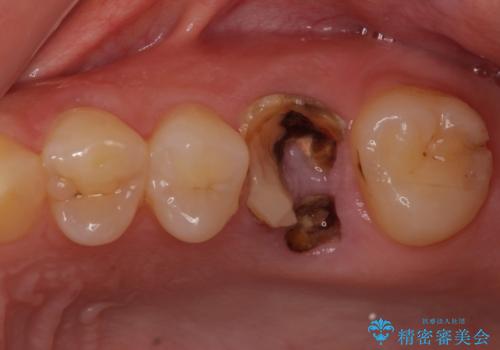

- 抜歯が必要と診断された奥歯を気にして来院された患者様です。

抜歯の上インプラントによる補綴治療を行うこととなりましたが、前歯の叢生も気になるとのことで並行して矯正治療を行うこととしました。

痛みがないので、ボロボロのまま放置していましたが、抜歯後は汚れが溜まりにくくなりスッキリとしたようです。